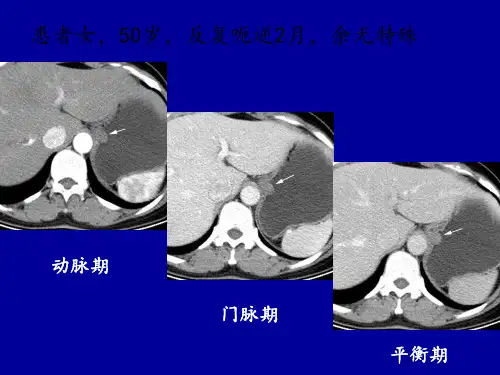

胃平滑肌瘤的影像学特点:

① 累及EGJ

② 密度及强化均匀,无坏死、钙化

③ 轻度强化(与背部肌肉相比)

④ 长径/短径>1.2(轴位测量)